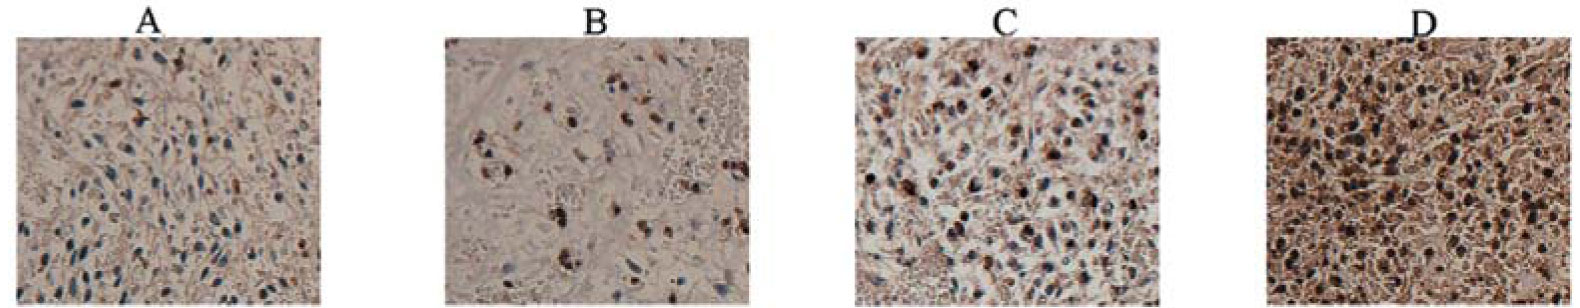

SPECIAL OFFER - Until February 29, 2016 – Save 10% on Kinases and Phosphatases Antibodies, and Peptides. Use promo code ENEWS0116 at time of order. Terms and conditions apply. LATEST PRODUCT CITATIONS - For a complete list of product citations, refer to the citation webpage. Cat. No. 250590 CD31 Antibody for IHC in porcine skin tissues Boekema BK. et al. 2014. J Mater Sci Mater Med. PMID 24178984. Effect of pore size and cross-linking of a novel collagen-elastin dermal substitute on wound healing. Cat. No. 250596 CD8 Antibody for IHC in mouse tumor tissues Qin W. et al. 2014. Oncol Rep. PMID 25242303. Modulated electro-hyperthermia enhances dendritic cell therapy through an abscopal effect in mice.  Cat. No. 250622 CMV-pp65 Antibody for in vitro assay with Vero cells Zanjani NT. et al. 2015. Antimicrob Agents Chemother. PMID 26643336. Abalone hemocyanin blocks the entry of HSV-1 into cells: a potential new antiviral strategy. Cat. No. 250683 HCV-Core Antibody for IF and IHC in HCV transgenic mouse liver tissues Islam MJ. et al. 2015. Biomed Res. PMID 26106045. Pol I-transcribed hepatitis C virus genome RNA replicates, produces an infectious virus and leads to severe hepatic steatosis in transgenic mice.  Cat. No. 250710 IGF-1 Antibody for WB in HepG2 cells and IHC in rat tissues Lee JY. et al. 2015. Mol Biotechnol. PMID 25555377. Production of recombinant human growth hormone conjugated with a transcytotic peptide in Pichia pastoris for effective oral protein delivery. Cat. No. 250839 PSD-95 Antibody for IHC in mouse brain tissues Cheng CF. et al. 2015. Pain. PMID 26121254. Nerve growth factor-induced synapse-like structures in contralateral sensory ganglia contribute to chronic mirror-image pain.